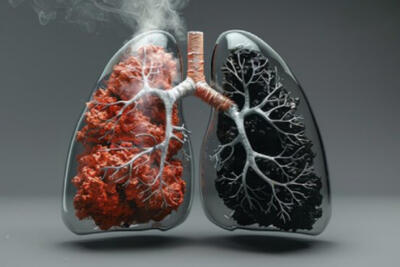

عامل اصلی ابتلا به بیماریهای ریوی چیست؟

جدیترین علل ابتلا به بیماریهای ریوی چیست؟

متخصص ریه هشدار داد: دخانیات یکی از اصلیترین عوامل بروز بیماریهای ریوی است.

شاه علامت بیماریهای ریه

متخصص ریه گفت: یکی از جدیترین علل ابتلا به بیماریهای ریوی مصرف دخانیات است.

نارسایی ریه در کمین سیگاری ها!

متخصص ریه گفت: یکی از جدیترین علل ابتلا به بیماریهای ریوی و نارسایی ریه مصرف دخانیات است. متخصص ریه گفت: یکی از جدیترین

شاه علامت بیماریهای ریه؛ سیگاریها دچار زجر تنفسی میشوند

متخصص ریه گفت: یکی از جدیترین علل ابتلا به بیماریهای ریوی مصرف دخانیات است.